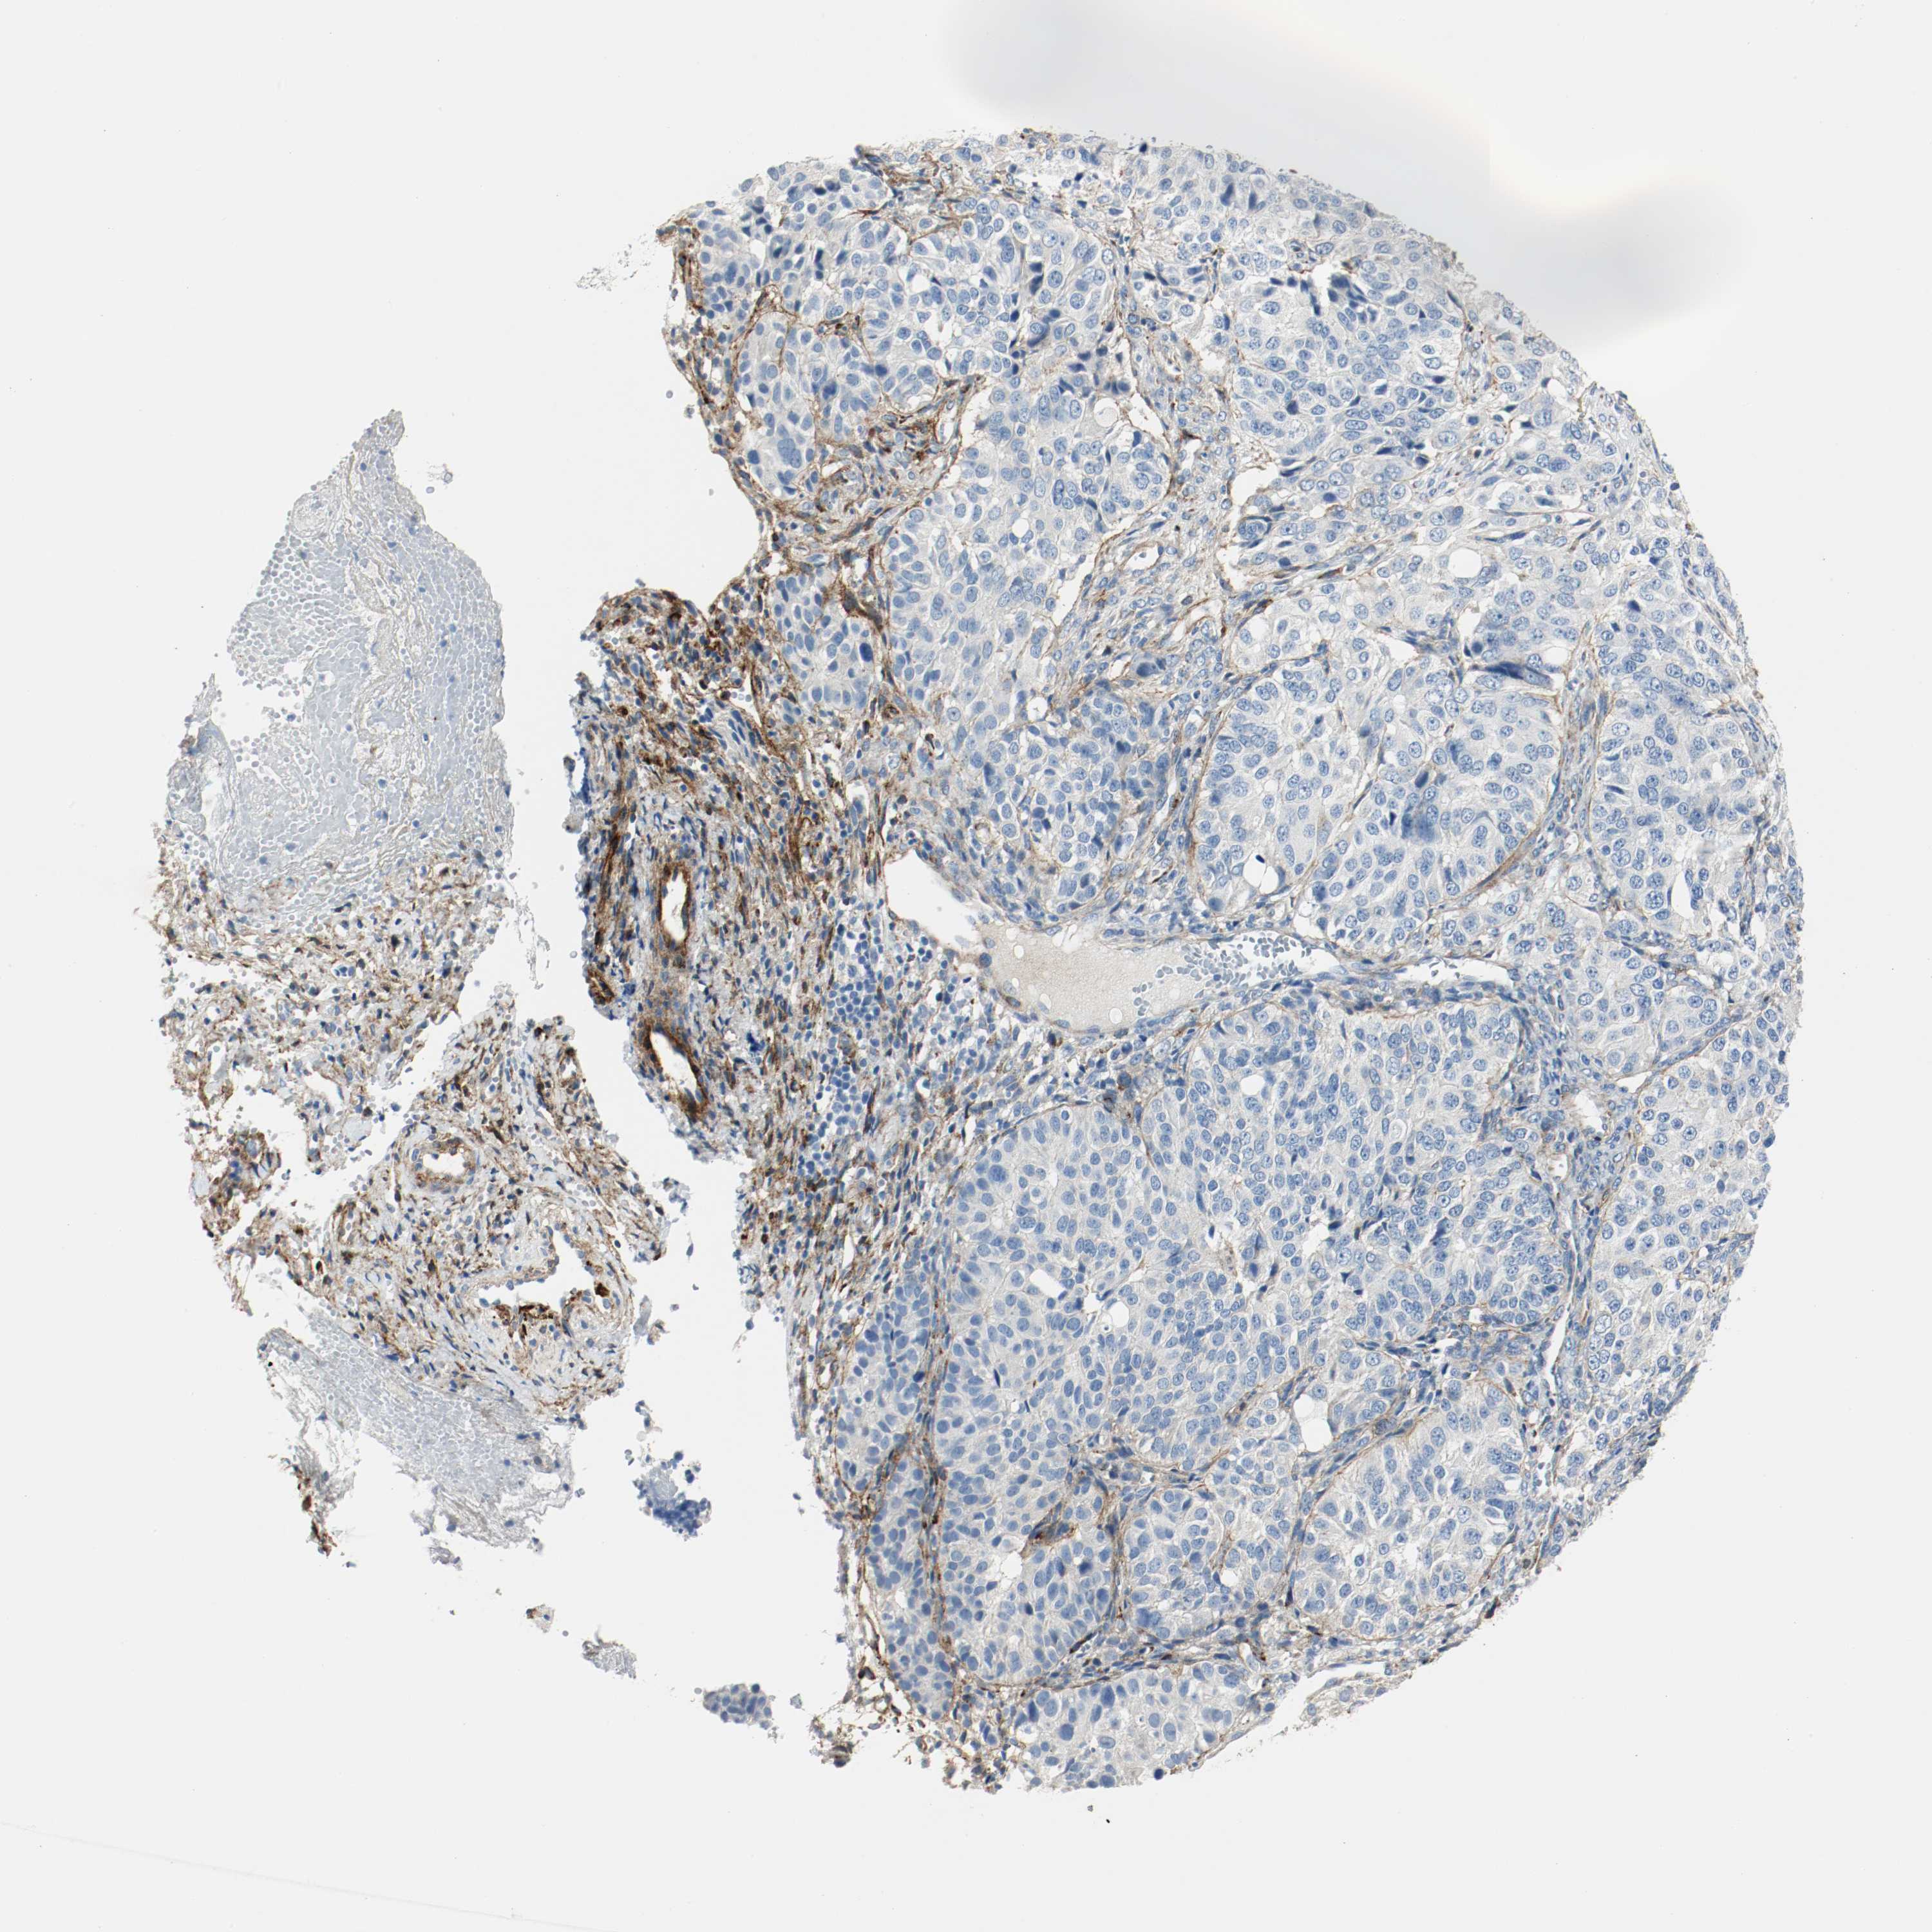

OVARIAN CANCER - Protein expressioni

A mouse-over function shows sample information and annotation data. Click on an image to view it in a full screen mode. Samples can be filtered based on level of antibody staining by selecting one or several of the following categories: high, medium, low and not detected. The assay and annotation is described here.

Note that samples used for immunohistochemistry by the Human Protein Atlas do not correspond to samples in the TCGA dataset.

Antibody stainingi

Antibody staining in the annotated cell types in the current human tissue is reported as not detected, low, medium, or high, based on conventional immunohistochemistry profiling in selected tissues. This score is based on the combination of the staining intensity and fraction of stained cells.

Each image is clickable and will lead to virtual microscopy that enables deeper exploration of all samples and also displays staining intensity scores, fraction scores and subcellular localization as well as patient and tissue information for each sample.

Antibody HPA004132

Staining

High

Medium

Low

Not detected

Carcinoma, endometroid

Carcinoma, NOS